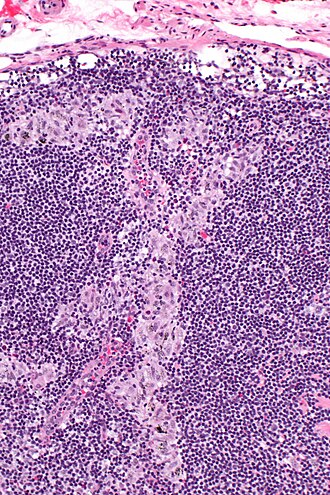

Sinus histiocytosis. H&E stain. | |

| LM | sinuses distended with histiocytes without atypia |

- Sinuses distended with histiocytes - key feature.

- Histocytes: abundant foamy cytoplasm, +/-anthracotic pigment and/or yellow bodies.

- Plasma cells increased.